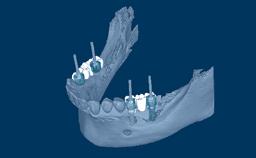

This clinical image shows three adjacent implants supporting single crowns. These provided the patient with a good functional outcome, but esthetics at the level of the implant emergence was only a secondary consideration.